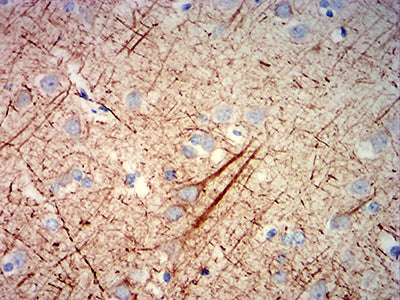

- Immunohistochemical analysis of paraffin-embedded human cerebrum tissues using NEFH mouse mAb with DAB staining.

- Immunohistochemical analysis of paraffin-embedded human cerebellum tissues using NEFH mouse mAb with DAB staining.

- Immunohistochemical analysis of paraffin-embedded human medulla oblongata tissues using NEFH mouse mAb with DAB staining.